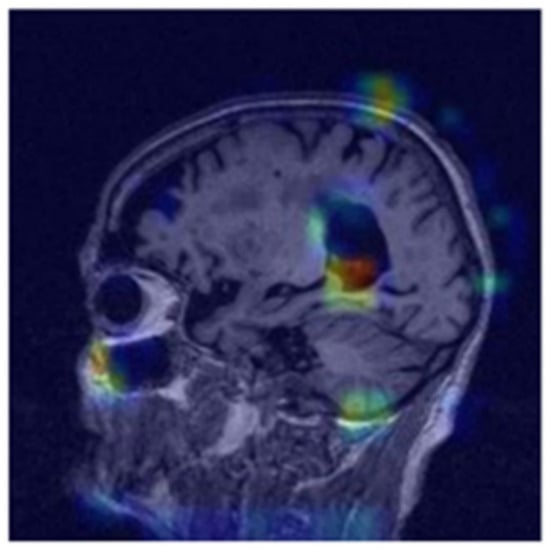

The confusion matrix in Figure 4 displays the network’s predictive performance on the three classes: NC (normal cognition), MCI (mild cognitive impairment), and AD (Alzheimer’s disease). Figure 3 is a visualization of the deep learning model’s performance where the highest training accuracy of 85% is displayed, calculated through Equation (5). The training process was stopped as the model had 0 out of 23,587,712 trainable parameters. Figure 4 visually represents the label predictions using the confusion matrix. One example from the test set produced a positive prediction for mild cognitive impairment (MCI), as shown in Figure 5. This image served as the input for our XAI experiments.

Additionally, we employed gradient-weighted class activation mapping (Grad-CAM) to visually identify significant areas that contribute to the model’s prediction. A convolutional neural network was utilized to analyze the image and extract features at various resolutions. The last layer of the network generates scores based on probabilities, which represent the classification of the image. The class score is calculated by

where ReLU, the rectified linear unit activation function, sets negative values to zero, k   is the sum of all activation maps, w k ( c ) represents the weights relative to the k -th activation map for class c , and A k is the k -th activation map. The ultimate standardized heat map accentuates the areas upon which our deep learning algorithm relies to provide predictions [8,9,25,26,27]. We employed a channel-wise self-attention mechanism to highlight significant features within each channel of the input tensor (Figure 8). This mechanism was accomplished through two convolutional layers with (1, 1) kernels that generate an attention map, which is then element-wise multiplied with the input tensor. The initial convolution layer, followed by a ReLU activation, formed an intermediate representation, while the subsequent convolution layer with a sigmoid activation created the attention weights. These weights adjust the emphasis on different channels, enabling the model to enhance or reduce specific features, thereby improving the learning process and overall performance [24,28,29,30].

Figure 8. Jet heatmap of positive values using self-attention for class-specific interpretability with gradient-weighted class activation mapping. The highest level of intensity in the heatmap is observed in close proximity to the hippocampus.